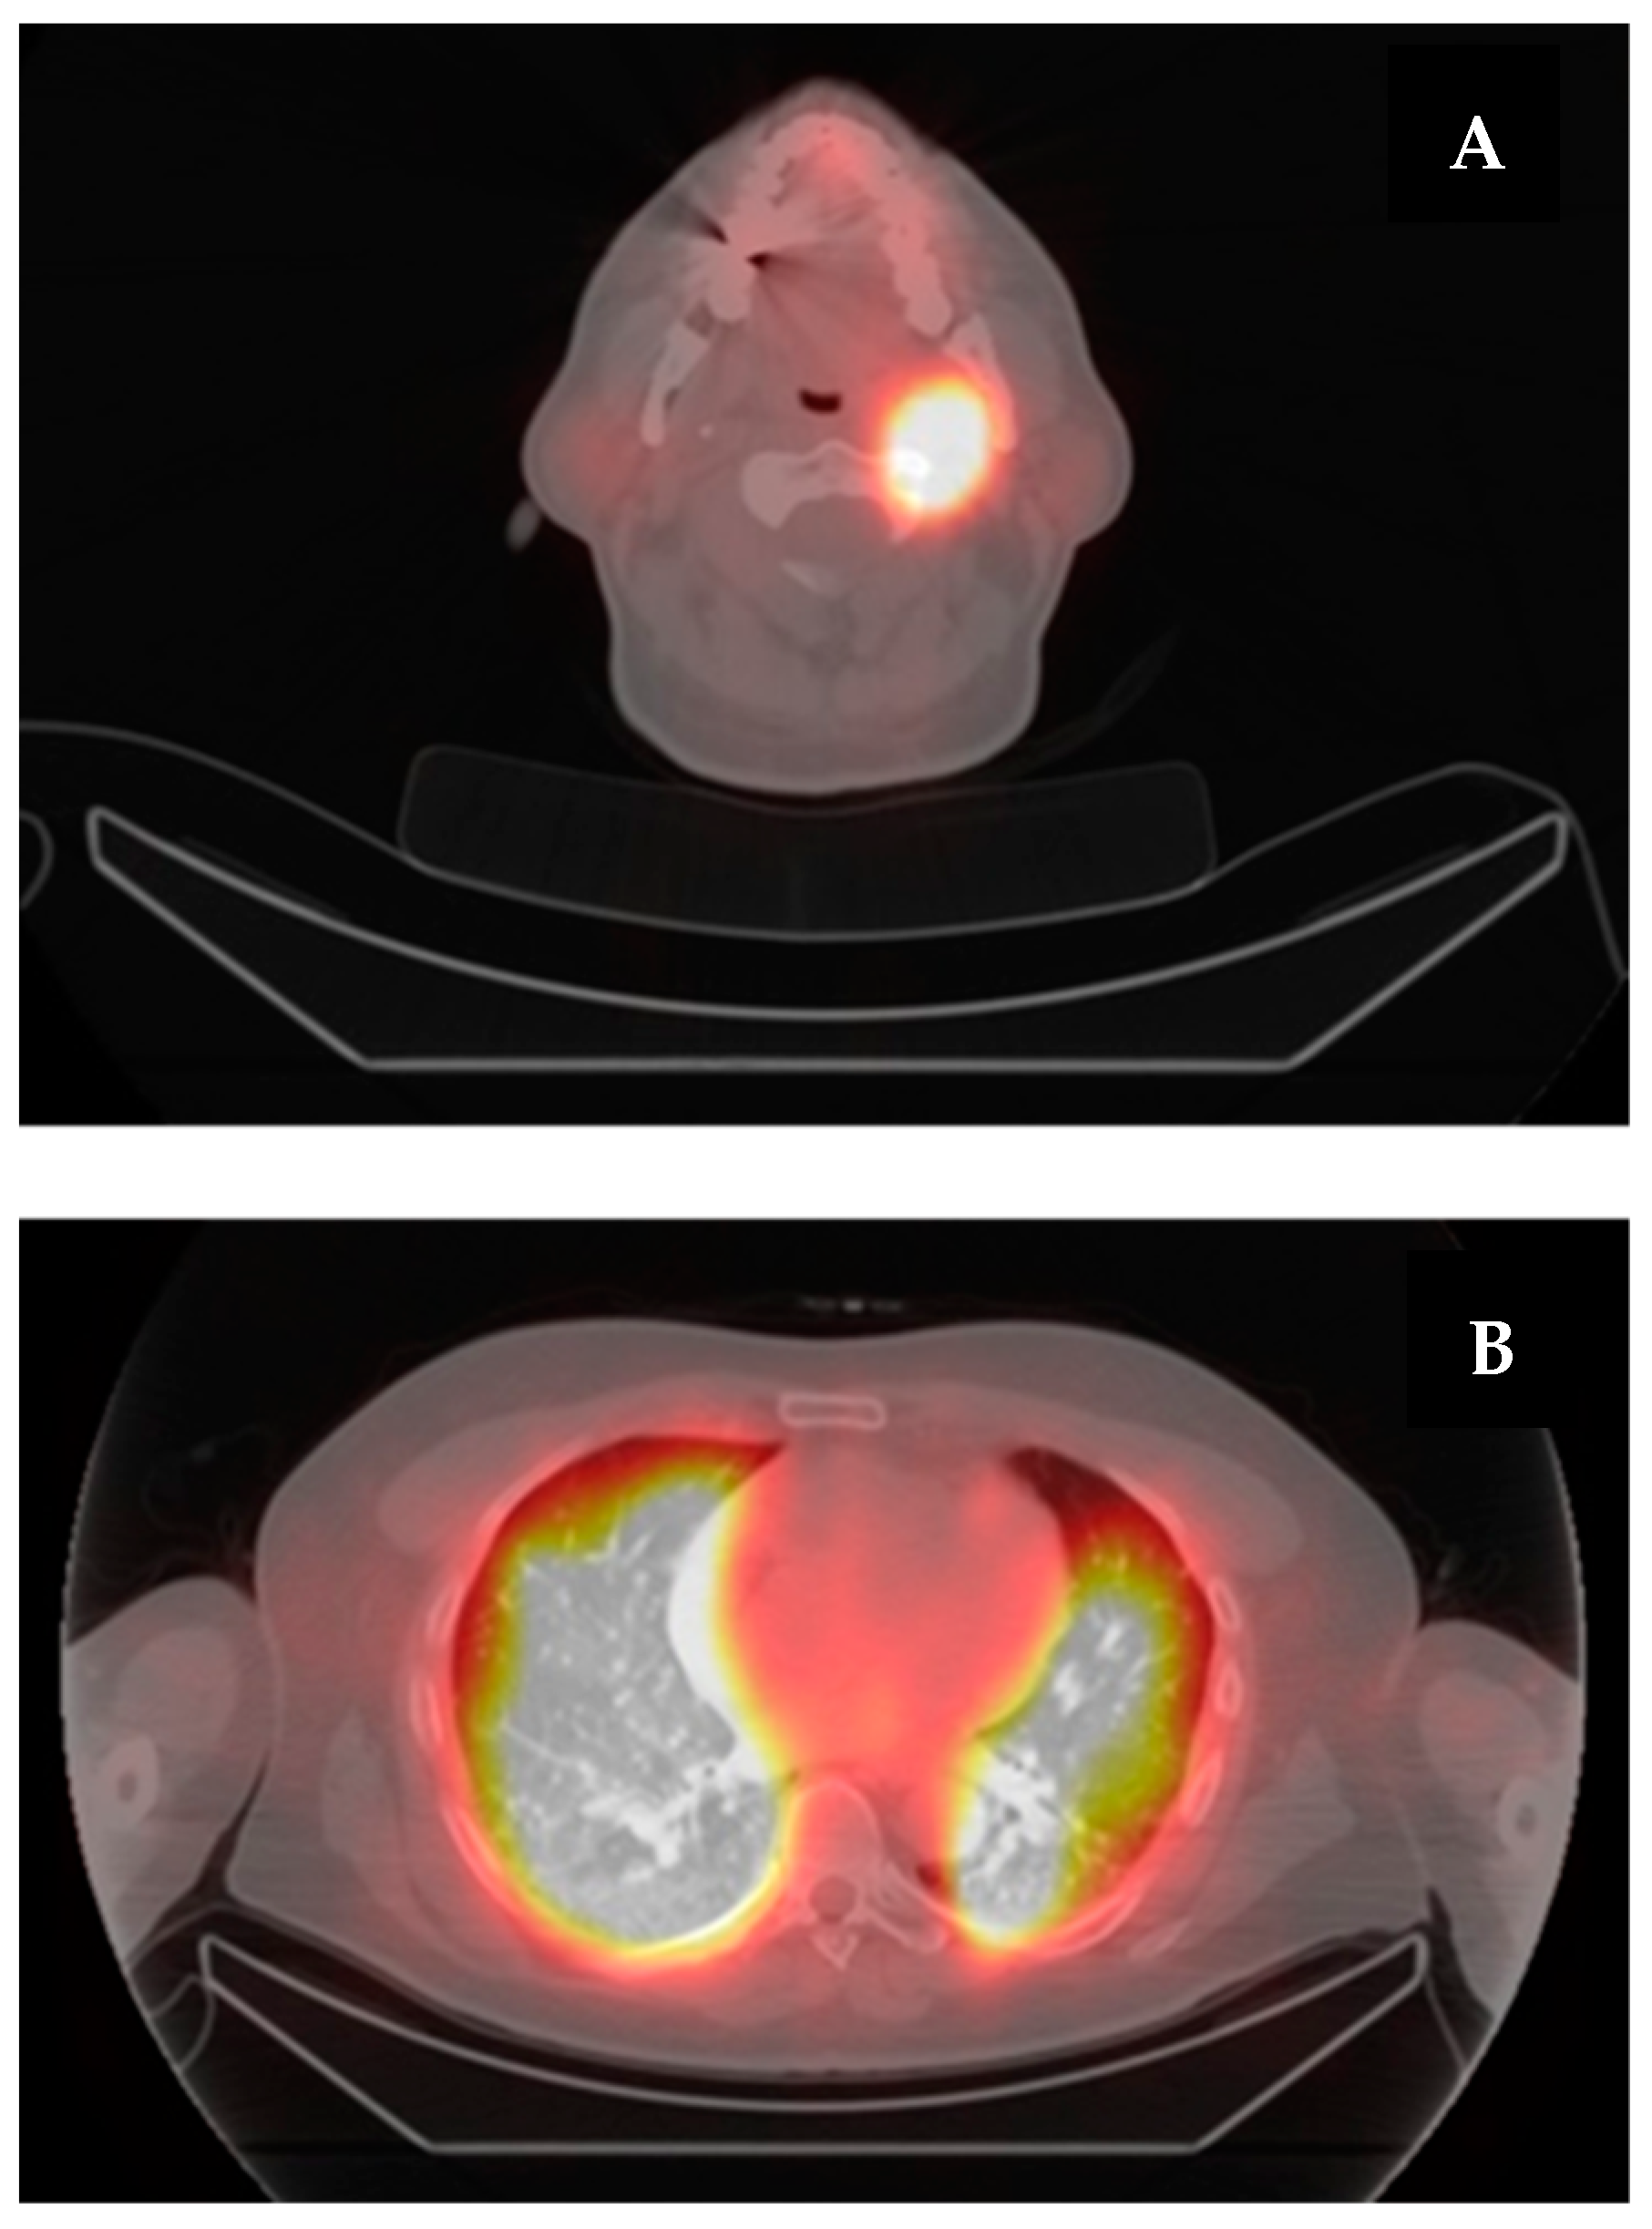

6. A Case of Re-Differentiation